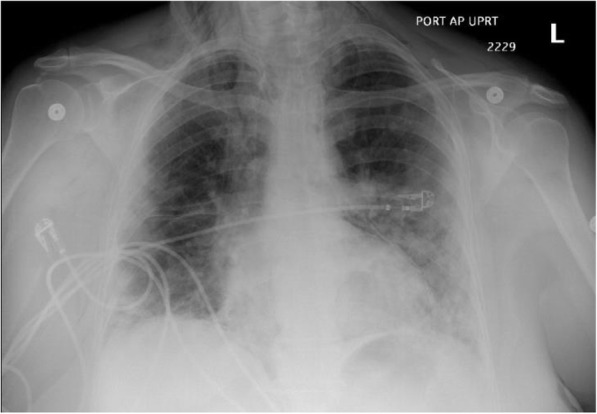

Fig. 1.

A frontal chest radiograph of Patient 1 showing interval development of pneumomediastinum, small pneumothoraces and subcutaneous emphysema